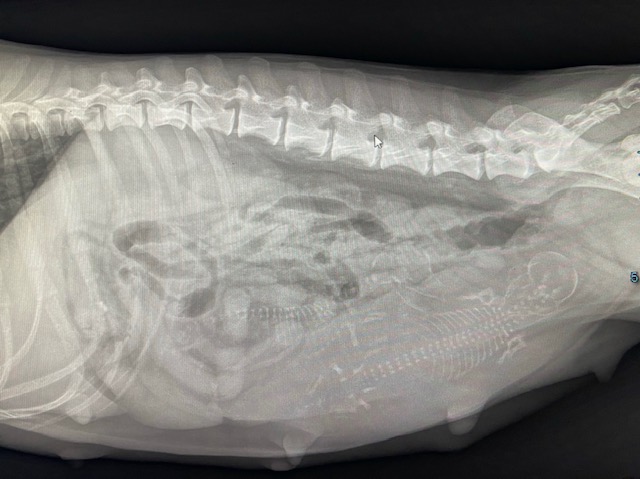

17.08.2023

Das Röntgenbild zeigt es ganz deutlich: Edda trägt zwei Welpen aus.

Für Edda wird alles langsam ein bisschen beschwerlich. Sie bekommt selbstverständlich weiterhin ihre tägliche Bewegung. Auch, wenn die Runden im Moment etwas kürzer ausfallen.

Eine gute Woche noch- dann kommen dei Kleinen.